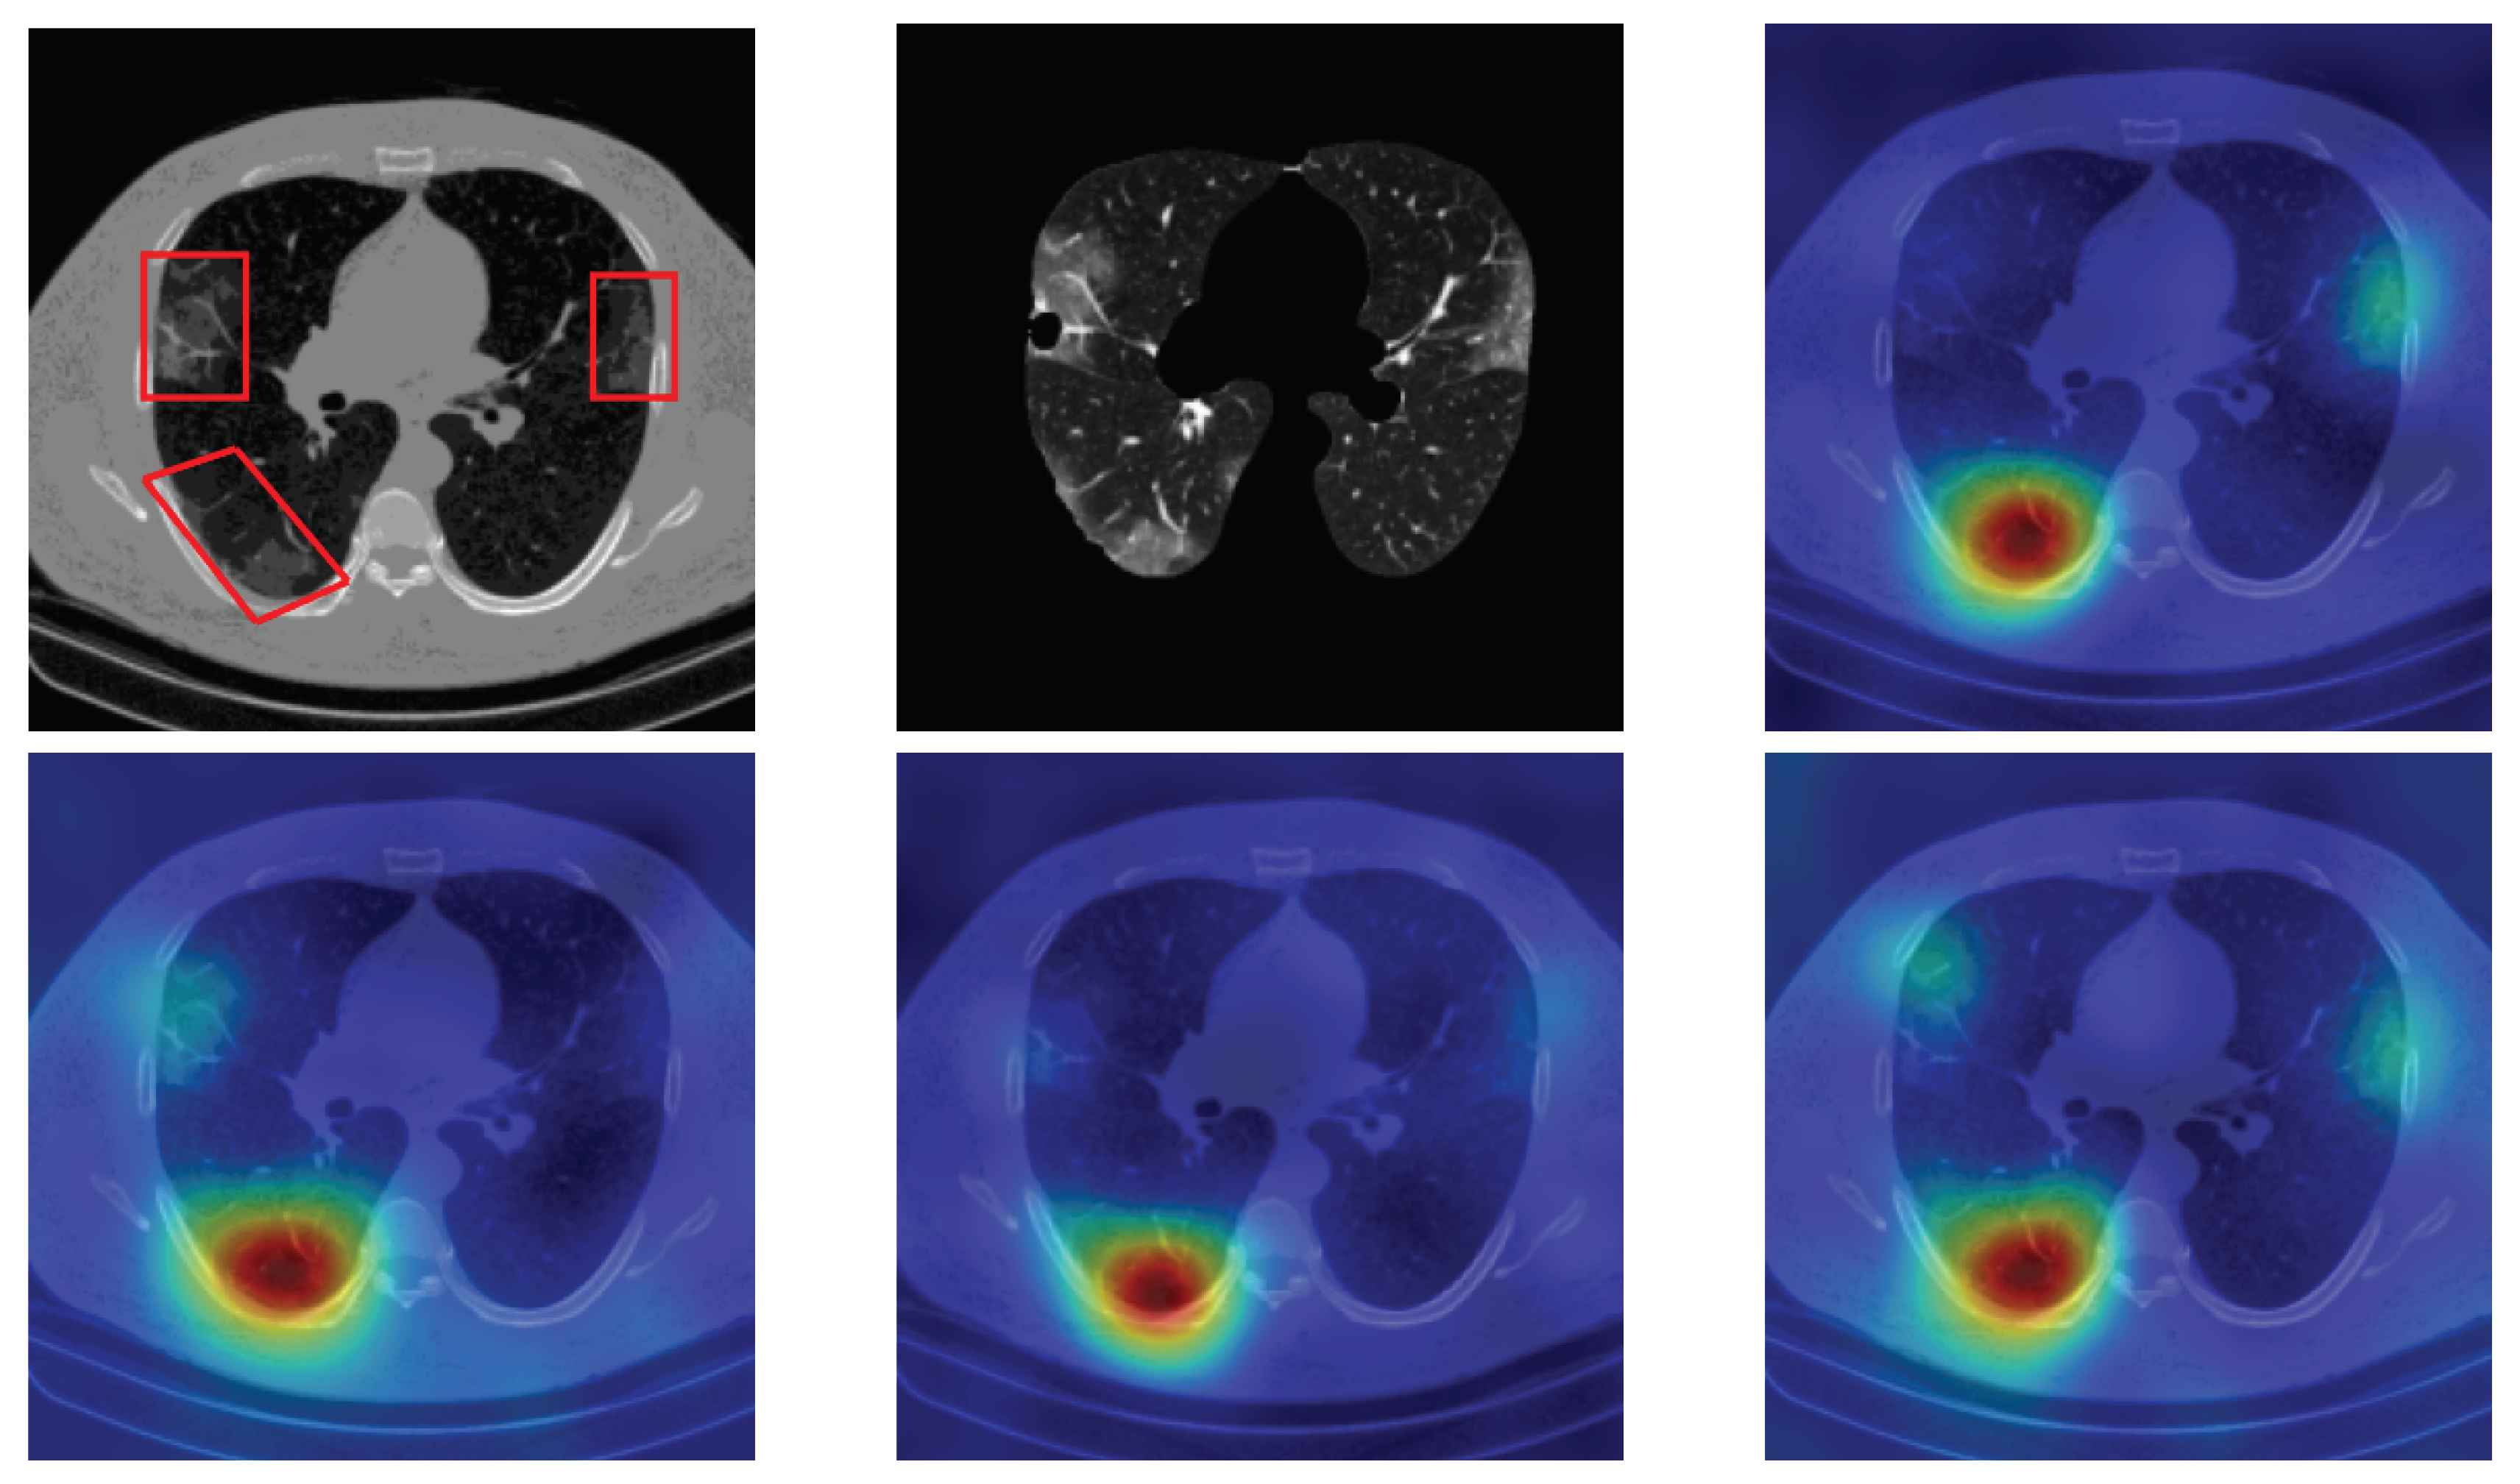

4.5. Heat Map

To have more intuition about the most important lung regions that the CNN architectures consider to classify the slice images, we used the randomized input sampling for explanations (RISE) approach [37]. Figure 13, Figure 14 and Figure 15 consist of two heat map examples of COVID-19, Cap, and normal cases, respectively. In the first example from Figure 13, we notice that despite the lung segmentation being not fully correct (it misses a considerable part of the infected region), the four CNN architectures gave more importance to the infected regions and to the lung regions in general. In the second example from Figure 13, we observe that the lung lobes were precisely segmented, and the heat maps of the four CNN architectures were well defined the infected regions, especially the Wide-Resnet-50 architecture. From both Cap examples in Figure 14, we notice that despite the lung segmentation missing considerable infected parts as well as the lung lobe regions, the heat maps of all CNN architectures give more importance to the infected region and to the lung lobes in general. This proves that the trained CNN architecture is able to define the regions of interest even when the lung lobes segmentation is not good. For the normal slice examples in Figure 15, the trained CNN architectures gave more importance to the lung lobes, especially the lower region, since the infection usually occurs there. The heat maps of COVID-19, Cap, and normal cases prove that the CNN architectures learned precisely where to look to identify the infection from the slice images.

Figure 13.

RISE heat map examples of COVID-19 slice images using the trained multi-tasks CNN architectures (ResneXt-50, Densenet-161, Inception-v3, and Wide-Resnet-50). The first example is shown in the first two rows, where the images represent the input slice image and segmented lung lobes results, followed by the heat maps of ResneXt-50, Densenet-161, Inception-v3, and Wide-Resnet-50, respectively. The second example is in rows 3 and 4.

Figure 14.

RISE heat map examples of Cap slice image using the trained multi-tasks CNN architectures (ResneXt-50, Densenet-161, Inception-v3, and Wide-Resnet-50). The first example is shown in the first two rows, where the images represent the input slice image and segmented lung lobes results, followed by the heat maps of ResneXt-50, Densenet-161, Inception-v3, and Wide-Resnet-50, respectively. The second example is in rows 3 and 4.